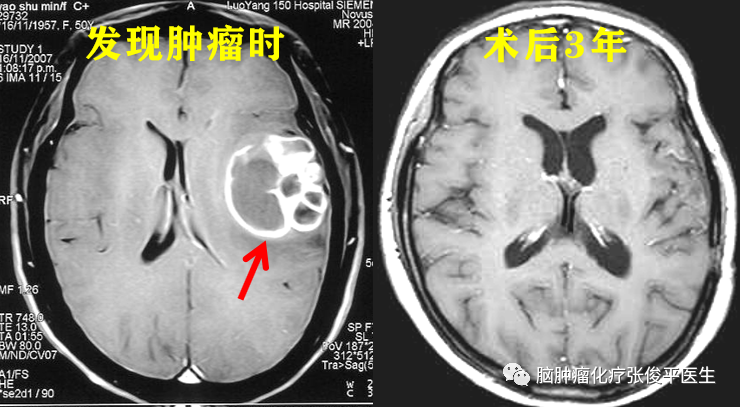

胶质母细胞瘤“抗癌明星”经验分享

她叫晓芳(化名)。2007年11月,50岁的晓芳出现言语不清、记忆力下降、头痛,核磁检查发现脑颞顶部占位。2007年11月26日在我院(首都医科大学三博脑科医院)手术,镜下全切肿瘤,术后病理结果为:多形性胶质母细胞瘤。术后晓芳做了放疗,放疗后在我院化疗病区接受个体化化疗共22个周期。2010年3月结束治疗后常规复查。

胶质母细胞瘤是恶性程度最高的4级胶质瘤,大多数病人活不到1年半。而晓芳在发病后3年多复查时肿瘤仍未复发,且生活质量非常好,同正常人一样。被誉为我科的“抗癌明星”!她为了让更多的病友同自己一样战胜恶性胶质瘤,特将自己患病经过、就医心得、心理调整、饮食搭配、身体锻炼等各方面经验同大家分享。下面是她当时写来的一封名为“感恩”的信件全文。

2013年4月,在晓芳抗癌5年半后(结束治疗后3年),肿瘤终究还是复发了。但是,通过及时正确的干预治疗、患者本人积极乐观的心态、健康有序的生活方式、家人无微不至的关怀和全身心的陪伴,晓芳又走过了将近5年的时光。她患癌后总生存期长达10年,且一直保持着较好的生活质量!